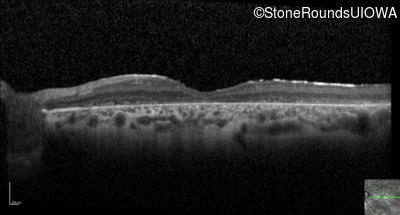

Optical Coherence Tomography - Right - 10/200

Exemplar / OCT Stack

Optical Coherence Tomography - Left - 10/160 -1